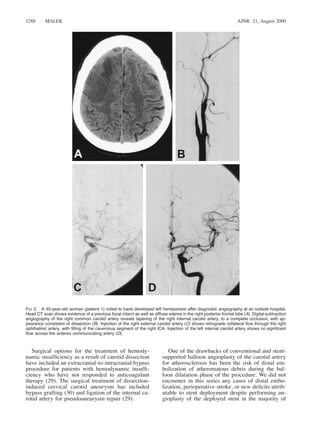

FIG 4. An 83-year-old man (patient 4) with a history of aortic dissection, which was surgically repaired 10 years previously, presents

with left hemispheric TIAs and episodes of aphasia. Digital subtraction angiography of the left common carotid artery outlines a chronic

extensive dissection, with antegrade flow through the true lumen and retrograde flow in the false lumen down to the aorta, by virtue of

the Venturi effect at the aortic arch (A, early injection; B, late injection). Two stents were placed in tandem overlapping fashion, followed

by postdeployment angioplasty, resulting in a near-complete elimination of the retrograde flow in the now-reduced false lumen (C, D).